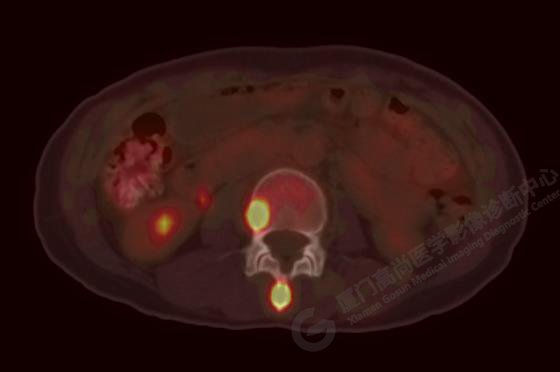

右肺上葉前段實(shí)性腫塊,大小約3.2x2.7x2.6cm,邊緣見毛刺、分葉,胸膜牽拉明顯,前段支氣管阻塞。FDG攝取增高,SUVmax,16.8;右側(cè)頸部Ⅳ區(qū)、右側(cè)鎖骨區(qū)、右肺門及縱隔淋巴結(jié)腫大, FDG攝取增高,SUVmax7.9;C2、L2椎體、右側(cè)第6肋骨、骶骨、髂骨、左側(cè)髖臼、腰椎體及附件骨質(zhì)破壞,SUVmax11.8。

影像診斷:右肺上葉周圍型肺癌并多發(fā)淋巴結(jié)、骨骼轉(zhuǎn)移。(TNM分期,T2aN3M1c Ⅳ B期)

病理診斷:低分化腺癌